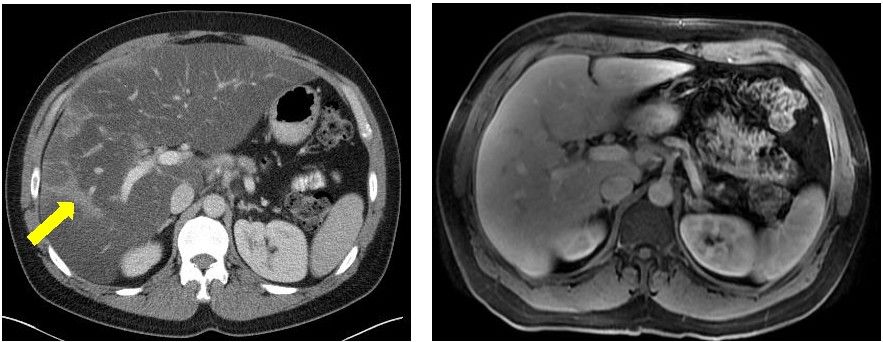

在2015年秋天,44岁的年轻人Doron Broman被诊断患有胰腺癌,生存期仅剩几个月。

确诊时

在接受最强的化疗方案FOLFIRINOX后,肿瘤虽然缩小,但是他无法承受强烈的副作用。他的主治医生,丹娜法伯癌症研究院的Kimmie Ng博士检测了Broman的肿瘤DNA的全部外显子序列,显示BRCA2基因的突变。他的医疗团队决定使用靶向Brac突变的药物,称为PARP抑制剂的olaparib(Lynparza) ,尽管这款药物当时仅获批用于卵巢癌。

在他使用奥拉帕尼六个月后,MRI和CT扫描显示没有癌症复发,生物标志物水平保持在正常范围。Ng说,只要癌症得到控制,他可以无限期地服用奥拉巴利,因为副作用很小。

FOLFIRINOX治疗5个月病灶明显缩小 vs olaparib治疗21个月病灶全部消失